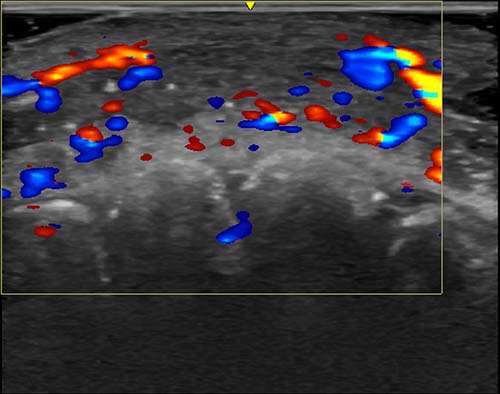

Figure 1. A serious complication from hyaluronic acid fillers is vascular occlusion—the disruption of blood flow in arteries—resulting from misplacement of filler material. If not promptly treated, vascular occlusions can cause necrosis and facial deformity.